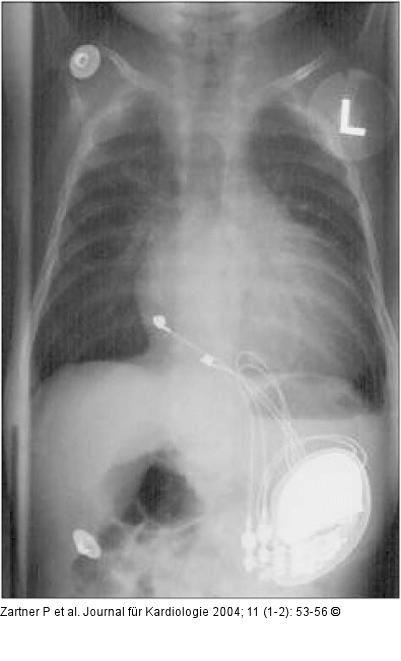

Abbildung 1: Herzschrittmacher - Kinderkardiologie Größenverhältnis eines Zweikammerschrittmachers mit unipolaren epikardialen Elektroden bei einem 3 Monate alten Säugling. Der Patient hatte nach einer Korrektur eines AV-Kanals einen kompletten AV-Block behalten. 4 Monate später kam es zur Perforation der Schrittmachertasche. Bei einem Gewicht von weniger als 10 kg wurde erfolgreich ein transvenöses bipolares Zweikammerschrittmachersystem implantiert. |

Größenverhältnis eines Zweikammerschrittmachers mit unipolaren epikardialen Elektroden bei einem 3 Monate alten Säugling. Der Patient hatte nach einer Korrektur eines AV-Kanals einen kompletten AV-Block behalten. 4 Monate später kam es zur Perforation der Schrittmachertasche. Bei einem Gewicht von weniger als 10 kg wurde erfolgreich ein transvenöses bipolares Zweikammerschrittmachersystem implantiert. |